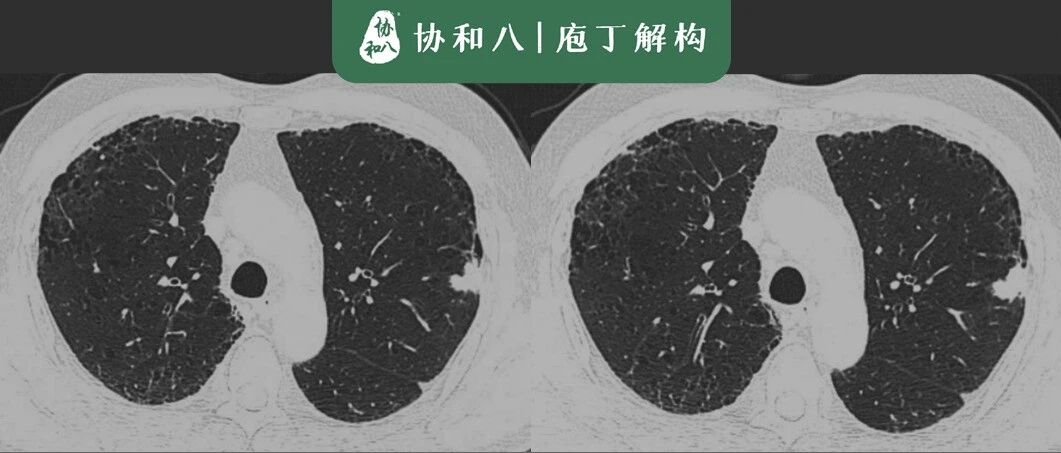

现病史:患者1年前无明显诱因出现血压偏高,最高达140/95mmHg,自诉曾查24小时动态血压提示高血压。近半年间断出现头晕,无视物旋转,现口服苯磺酸氨氯地平片、拜阿司匹林、瑞舒伐他汀等药物治疗,平素纳眠可,二便调,舌质淡红,苔薄白,脉沉细。既往史:脑梗病史1年,高脂血症病史、胆脂瘤病史(具体不详);否认其他病史。BP:130/90mmHg。